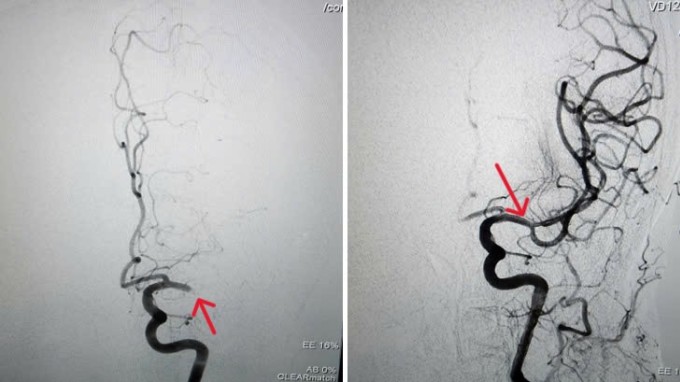

Kết quả chụp CTA mạch máu não cho thấy người bệnh bị tắc hoàn toàn động mạch não giữa bên trái tại vị trí nhánh M1,chiều dài khoảng 10 mm. Người bệnh được can thiệp nội mạch,loại bỏ cục huyết khối đang làm tắc động mạch não. Can thiệp nội mạch là phương pháp ít xâm lấn,hiệu quả cao và an toàn,nhất là với bệnh nhân đột quỵ cao tuổi,rung nhĩ,theo bác sĩ Phụng.

Động mạch não giữa bên trái của cụ Năm bị tắc hoàn toàn (hình trái) và tái thông sau khi can thiệp nội mạch (hình phải). Ảnh: Bệnh viện cung cấp

BS.CKI Dương Đình Hoàn,Trưởng Đơn vị Can thiệp Thần kinh,Trung tâm Chẩn đoán Hình ảnh và Điện quang Can thiệp,Bệnh viện Đa khoa Tâm Anh TP HCM,cho biết dưới sự hỗ trợ của máy chụp mạch máu số hóa xóa nền DSA hiện đại,êkíp can thiệp luồn ống thông nhỏ vào động mạch đùi tại vùng bẹn,bên trong có thêm vi ống thông siêu nhỏ được gắn dụng cụ chuyên dụng. Sau đó,di chuyển trong lòng mạch,nhanh chóng tiếp cận vị trí cục huyết khối ở não.

Từ đây,bác sĩ hút toàn bộ huyết khối ra ngoài,góp phần tái thông mạch máu não chỉ sau 15 phút can thiệp. Ưu điểm của phương pháp này là giảm tối đa tổn thương não,hạn chế các khiếm khuyết thần kinh sau đột quỵ.